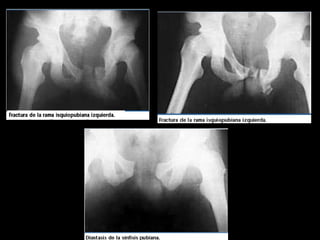

Simples, o tipo A: son las más

frecuentes, ocurren en 58% de

los casos, son estables y

generalmente no dejan

secuelas

Inestables, o tipo B: menos frecuentes; ocurren en

22% de los casos. Hay inestabilidad parcial o

rotacional del anillo pelviano, causada por apertura

de una hemipelvis o por cierre de una hemipelvis

contra la otra. No se compromete la articulación

sacroilíaca posterior,

Complejas, o tipo C: ocurren en 20% de los casos; su letalidad se debe a

las lesiones agregadas, de modo que requieren estabilización de urgencia y

tratamiento definitivo en un centro especializado. Son verticalmente

inestables, con separación completa de una hemipelvis